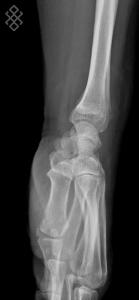

Radiographie du Poignet

Vous serez installés en position debout avec la main posée sur la table d'examen.